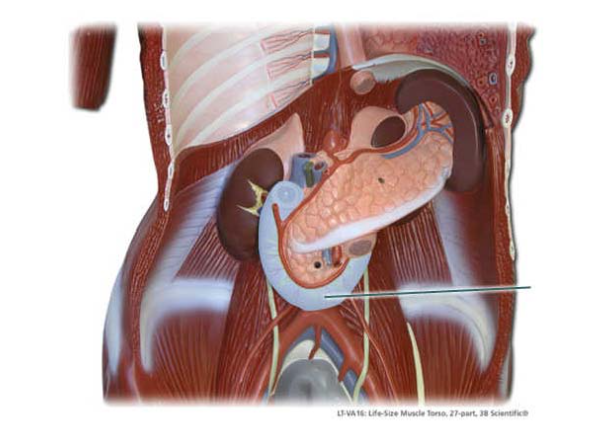

Into which organ does the highlighted structure empty?

stomach

The highlighted structure separates the stomach from the…

duodenum